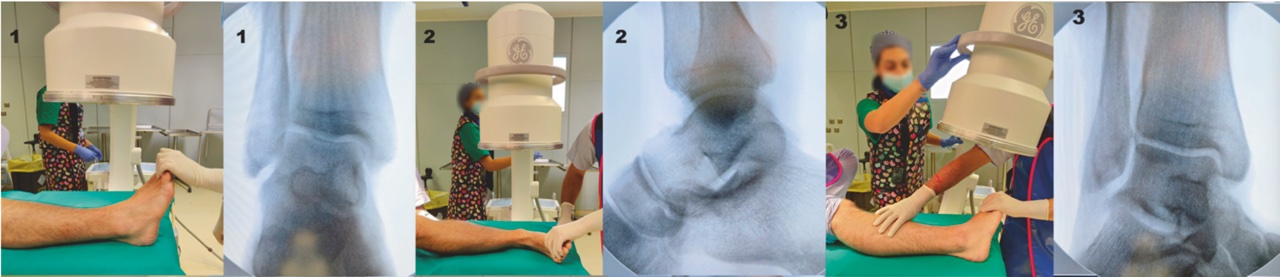

È necessario eseguire radiografie della caviglia in proiezione antero-posteriore (AP), laterale e nella proiezione del mortaio (intrarotazione della caviglia di 15-20°), nonché radiografie del piede in proiezione AP, laterale e obliqua (Fig. 2).

Proiezione di Canale e Kelly: fornisce una visualizzazione ottimale del collo dell’astragalo. Viene acquisita con la caviglia in equino: il piede del paziente viene appoggiato sulla cassetta radiografica e pronato di 15°, mentre il fascio radiogeno viene diretto cranialmente con un’inclinazione di 15° rispetto alla verticale. Questa proiezione è stata descritta per la valutazione di deformità post-traumatiche ed è difficile da acquisire nel contesto acuto ma può essere utile da acquisire intraoperatoriamente.